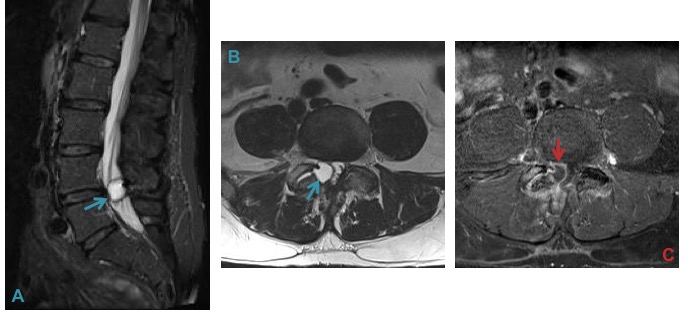

f) Synovial Cyst – may cause spinal canal stenosis.

Spinal and lateral recess stenosis is often caused by synovial cysts. Detection is aided by fat suppression (A) and lack of central enhancement (C). L4-L5 is the commonest location.